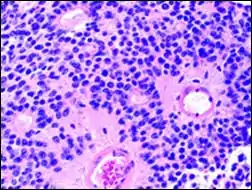

Micrograph of pineocytomatous/neurocytic pseudorosettes

Pineocytomatous/neurocytic pseudorosettes

Histologic features of these two tumors are virtually identical, including their tendency to form neuropilrich rosettes, referred to as pineocytomatous/neurocytic rosettes in central neurocytoma. Both are quite similar to the Homer Wright rosette, but they are generally larger and more irregular in contour. The cells of the pineocytomatous/neurocytic rosettes are also considered to be much more differentiated than the cells forming Homer Wright rosettes in that the nuclei are slightly larger, more rounded, much less mitotically active, and paler or less hyperchromatic. In rare cases, these rosettes may aggregate in a sheet of back-to-back clusters resembling field stone pavement.[2]